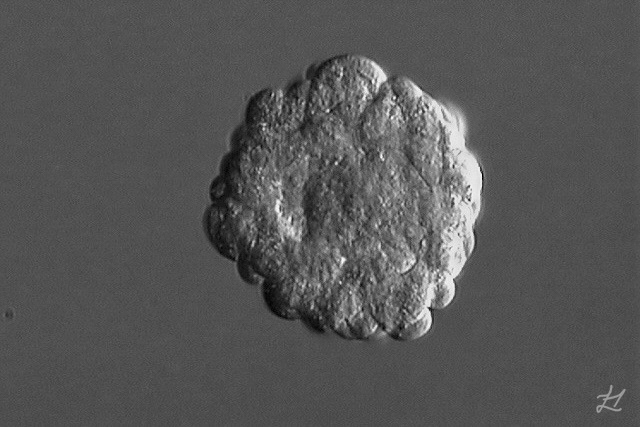

That was the day the embryo – the one that turned out to be Kaydes – was transferred into my womb at FA. A microscopic, blastocyst bundle of potential, full of unknowns and impossibilities. Yet somehow, with some doubts, she stuck in like glue. And now, four years later, she’s my best friend, my little +1, my greatest adventure!